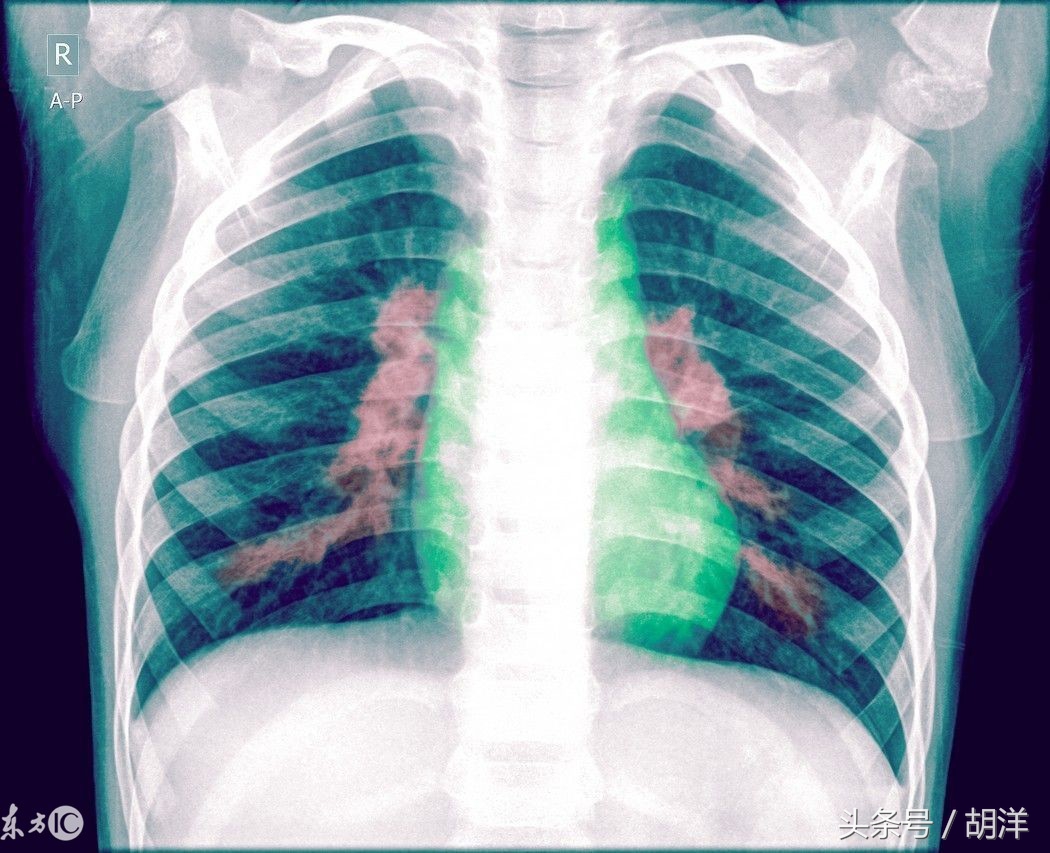

肺炎是内脏重要器官中最常见的一种感染性疾病

这和肺的特点有关,肺主要起到吐故纳新,摄入空气排除废气的作用,由2亿个肺泡组成基本的功能单位,每一个肺泡都有一个终末细支气管供应空气,这些终末细支气管在逐级汇总成总的气管与外界相通,人体除了肺,还有肠道也和外界相通,但和肺不同,肠道内常年有大量的正常菌群寄生,这些正常菌群天然排斥外界的病原体,客观上起到了保护肠道不守外界感染的作用,而肺是一个无菌器官,主要靠上呼吸道的一些过滤结构比如鼻毛以及下呼吸道的免疫屏障来保持,这些结构本身存比较脆弱,很容易受到身体因素比如劳累着凉有毒有害物质的侵害而功能下降,这就决定了肺部很容易受到细菌的侵扰,有的人表现为肺炎,有的人则毫无症状肺部就已经被感染过了,这就是很多人体检发现肺部有纤维条索等疤痕表现的原因。

肺炎的症状多而复杂,根据不同的病原体和疾病的严重程度会有不同的表现,下面介绍一下肺炎的不同表现。